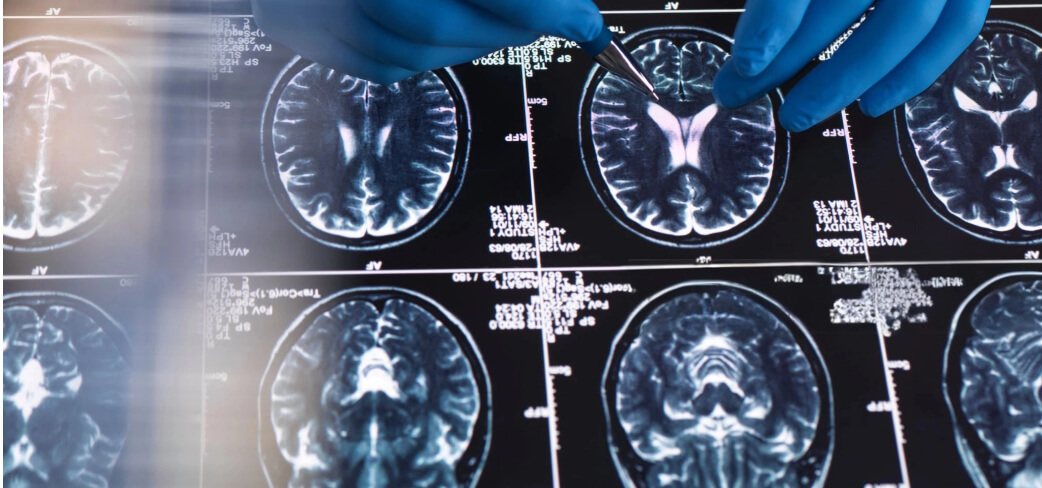

Il nuovo studio ha seguito tre pazienti sottoposti ad amputazione di una mano, con risonanze magnetiche funzionali effettuate prima e dopo l’intervento. I ricercatori hanno chiesto ai partecipanti di muovere le dita o arricciare le labbra, così da osservare l’attivazione delle aree cerebrali coinvolte. I risultati hanno mostrato una sorprendente stabilità: anche a mesi o anni dall’amputazione, la regione cerebrale corrispondente alla mano continuava ad attivarsi quasi come se l’arto fosse ancora presente.

Questa evidenza mette in crisi la vecchia idea di una riorganizzazione radicale della corteccia somatosensoriale. In realtà, la mappa del corpo resta intatta e non viene invasa dalle aree vicine, come quella delle labbra. Il fraintendimento, spiegano gli studiosi, deriverebbe da limiti metodologici delle ricerche precedenti.